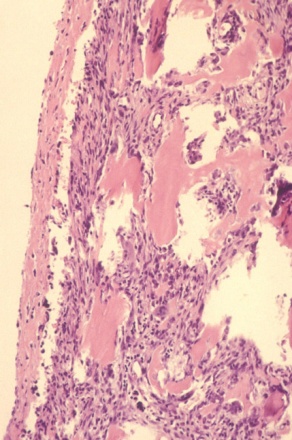

Aneurysmal Bone Cyst